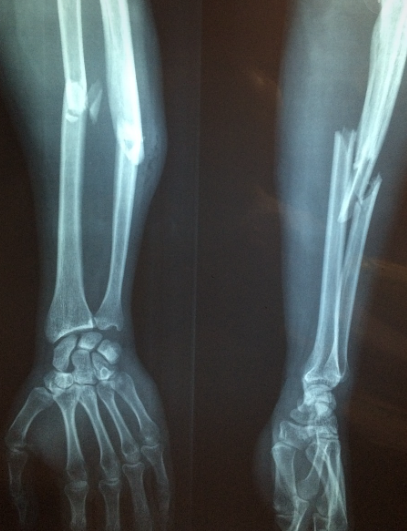

② 다발성 골절(Polytrauma)

교통사고 등으로 인해 여러 부위의 뼈가 동시에 골절되면 출혈량이 많아지고, 이로 인해 저혈압과 쇼크가 발생할 수 있습니다. 이러한 상태가 적절히 관리되지 않으면 장기 손상과 패혈증으로 이어져 생명을 위협할 수 있습니다.